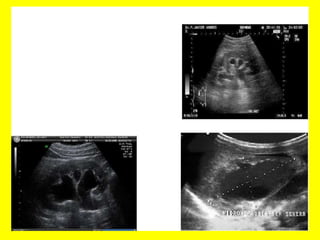

Ecografía abdominal. Es el examen no invasivo

más utilizado en la actualidad, pues permite

confirmar o descartar la obstrucción a nivel

renal y a diferenciar con otras causas los

defectos de llenado, observando en la

urografía, tales como tumores o coágulos.

Tomografía axial computadorizada. Es útil para

la identificación de cálculos levemente radio-

opacos.